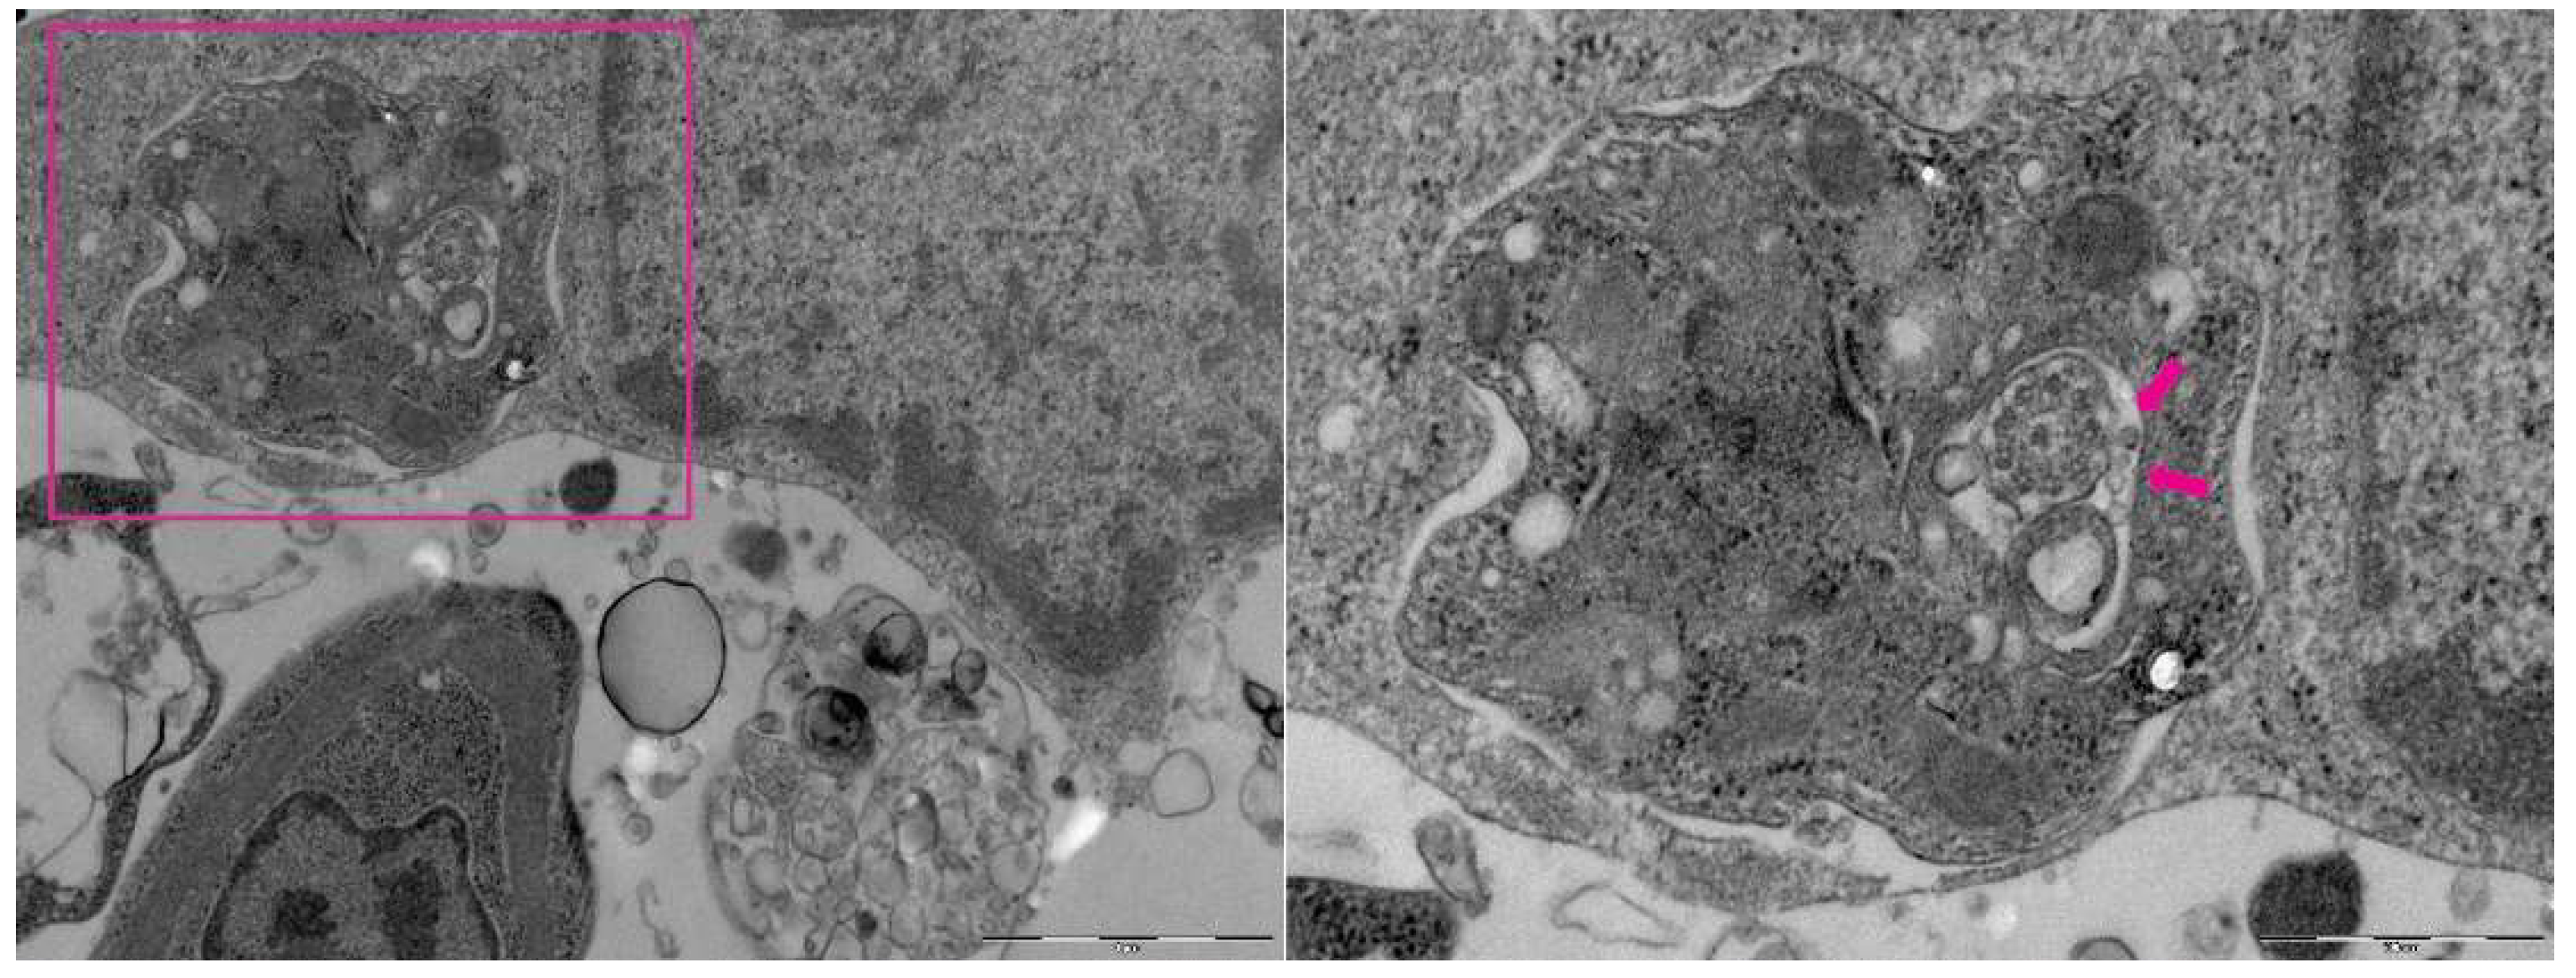

3.2. Macrophages infected with Leishmania (Leishmania) amazonensis examined by Transmission Electronic Microscopy TEM